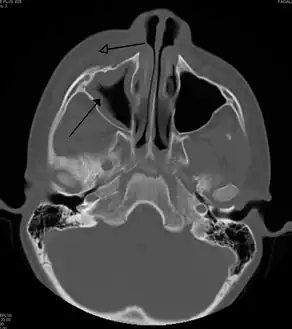

CT of chronic sinusitis

CT scan of chronic sinusitis, showing a filled right maxillary sinus with sclerotic thickened bone.